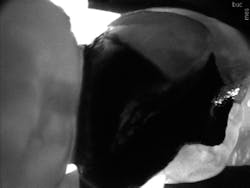

For example, 18-year-old twins presented to my office recently. The referring practice was not able to supply clinically readable digital x-rays. To get the twins comfortable and start the diagnostic process, I used CariVu. I was able to determine that they did not have occlusal or interproximal caries, and consequently, they had no need for treatment at the time (figures 2 and 3). These young men remarked, "Dr. McKibben has all of the latest technology." They will probably even tell their friends and family. Although I am an older practitioner, I still want to maintain a reputation of being on the cutting edge of innovation. CariVu, along with my other technologies such as CAD/CAM, helps with that perception.

Figure 2: One of the twins' CariVu images that shows no caries. Note the lighter enamel border around the darker dentin.

Figure 3: Image of interproximal caries from another patient. Caries is more porous, so appears darker.